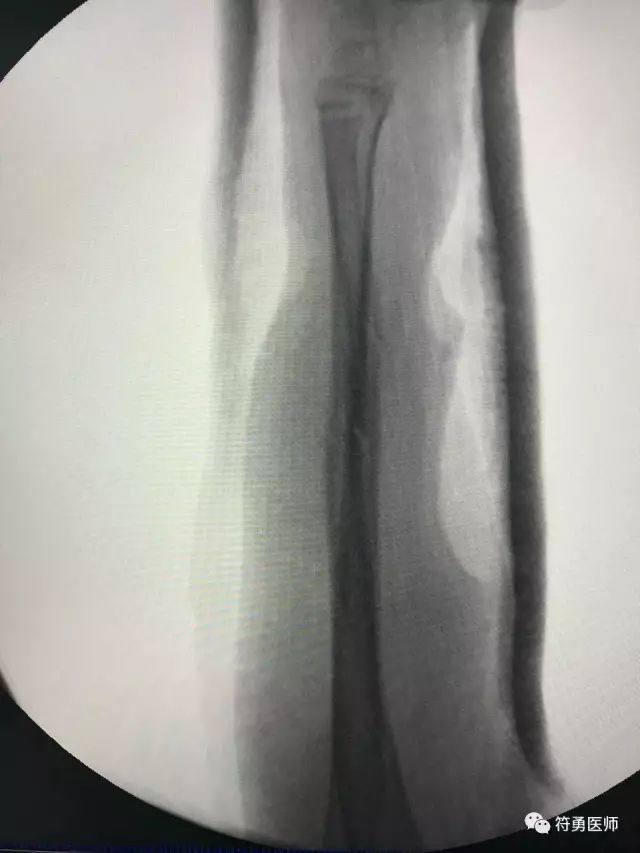

上图:摔伤后第二次找外院的医生接骨后正位好转,孩子受罪疼痛折腾,但看看下图的侧位仍然位置不理想

上图:摔伤后第二次找外院的医生接骨后正位好转,孩子受罪疼痛折腾,但看看上面的侧位仍然位置不理想。

上图:经过南华附二小儿骨科中心精心复位接骨之后,位置完美。

采用祖国医学五千年经典神奇手法接骨,借鉴西医新时代先进顶尖理念复位,在三维C臂动态检测下,成功给孩子复位接骨,并采用独特的手法及三点衬垫固定技术,不开刀,不手术,纯手法,接骨成功。